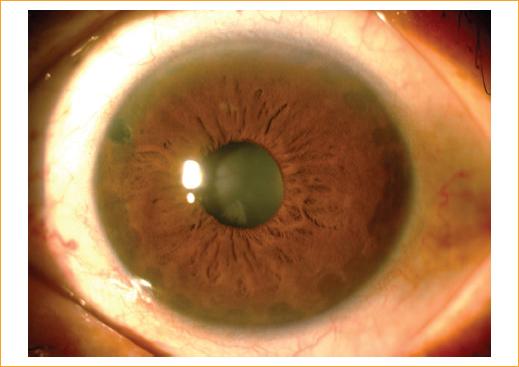

Se sospechó el diagnóstico de probable configuración de iris plateau en el ojo derecho y probable síndrome de iris plateau en el ojo izquierdo, por lo que se solicitó una ultrabiomicroscopia (UBM) de segmento anterior que corroboró el diagnóstico de iris plateau en ambos ojos (Fig. 1).

Figura 1 Ultrabiomicroscopia de ojo derecho y de ojo izquierdo con ausencia del surco ciliar y anterorización de los procesos ciliares.